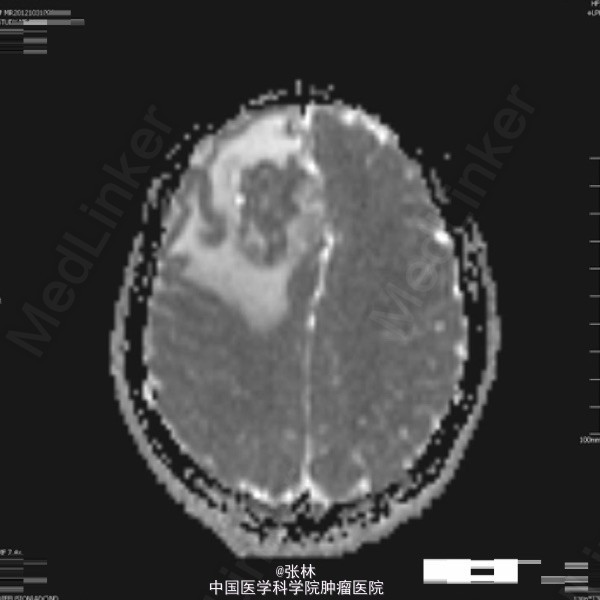

42岁女性,10余天前无明显诱因出现头痛,并呕吐胃内容物,双眼视物模糊。影像学表现:右侧额叶见一不规则形占位性病变,大小约为3.7×4.0×4.5cm,T1WI呈等、低信号,T2WI呈等、高信号,DWI仍呈高信号,周围脑组织少量水肿,增强扫描后病变呈明显强化,边缘水肿无强化。 病理: 镜检:肿瘤细胞弥漫增生,呈乳头状、腺样,细胞核卵圆形,深染。 免疫组化示:GFAP(散在细胞+)、Vimetin(+)、S100(-)、CK(+)、EMA(+)、ki-67(5%+)、CD99(部分+)、CD56(+)、NF(-)、CD34(-)、Hepa(-)、AFP(-)、mammaglobin(-)、RCC(-)、WT-1(-)、CD10(-)、CK7(-)、CK20(-)、Villin(-)、CR(-)、MC(-)、MOC31(-)。及少许脂肪组织,上皮混合组成。 讨论: 室管膜瘤来源于脑室与脊髓中央管的室管膜细胞或脑内白质室管膜细胞巢的中枢神经系统肿瘤。在胶质瘤中占6%,男多于女,多见于儿童及青年,约75%位于幕下,幕上仅占25%。文献报道幕上室管膜瘤75 ~85 %位于脑室外。脑实质内室管膜瘤起源于室管膜细胞嵴,可能是神经管内折叠时形成畸形的结果,好发部位为丘脑,其次为额叶、颞叶、顶叶。实性多见于成人,囊性多见于青少年。 幕上室管膜瘤以头痛、呕吐、嗜睡、厌食及复视等颅高压症状为主,多有局部运动功能障碍和癫痫。